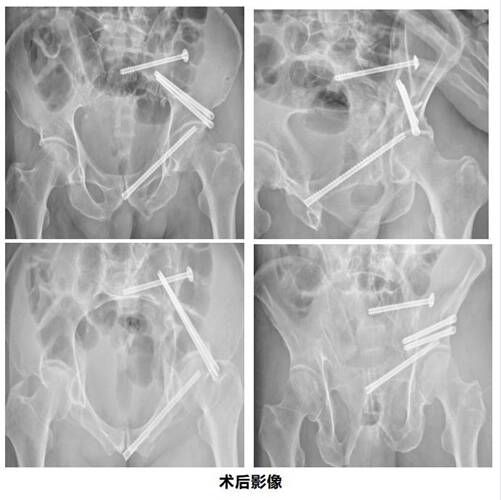

△患者創(chuàng)傷影像

蔣大爺入院后,因劇烈疼痛表情一直極為痛苦,不能活動(dòng),很快出現(xiàn)墜積性肺炎等并發(fā)癥,并且因大小便困難,不愿意進(jìn)食,蔣大爺精神萎靡,全身情況消耗性變差。家屬迫切希望能給予患者積極治療,緩解疼痛。

骨盆承擔(dān)了保護(hù)盆腔重要臟器的任務(wù),同時(shí)也是承接軀體上半部和下半部的“連接器”。它的周?chē)蟹浅6嗟难芎蜕窠?jīng),一旦發(fā)生嚴(yán)重骨折,可能會(huì)造成諸如失血性休克,膀胱尿道損傷,神經(jīng)損傷等后果,因此骨盆骨折又被稱(chēng)為“骨折之王”。